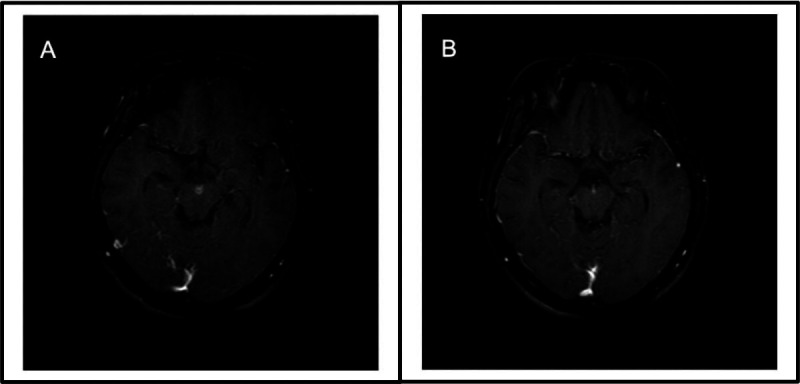

Results: We described the clinical, microbiological, radiological and serological features of five patients with a TBM-like presentation eventually diagnosed with MOG-associated meningitis. Symptoms included headache, vomiting, visual impairment and weakness. Three patients showed normal MRIs and two patients showed MRI findings consistent with demyelination. Serum MOG antibody testing was positive only on serial testing of all five patients. The final diagnosis was MOG-associated meningitis in two patients and MOG-associated meningoencephalitis in three patients.

Abstract Image